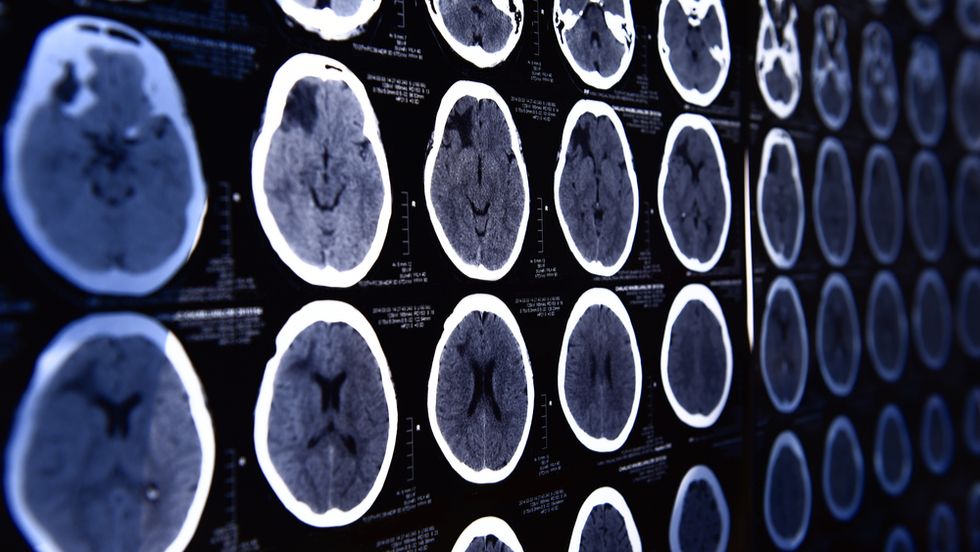

The biology of fear

First, some facts: There is no single fear switch for humans; responding to threats involves multiple areas of the brain. We’re not 100% how, but scientists have found the amygdala—almond-shaped bundles of neurons buried deep in the brain, just above the brain stem—central to the process.

“When you sense something potentially dangerous, the amygdala sends excitatory signals to other parts of the brain, effectively saying, ‘Hey everyone, pay attention!’” says Bambi DeLaRosa, a researcher on threat processing. The areas of the brain associated with language and memory also become active in the face of fear. If the amygdala sounds the alarm, the other areas help evaluate the threat level and how you respond.

But people with the extremely rare Urbach-Wiethe disease have calcium deposits in their brains, making it impossible for them to process fear. Studies have found their amygdala completely calcified, so there’s nothing to signal for fear signs like sweating palms or a racing heart to begin. Researchers have identified only 400 people in the world with this condition.